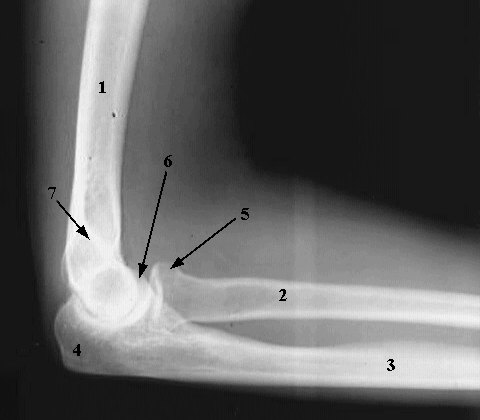

Upper Limbs: Elbow Flexed:

1. Humeral Shaft

2. Radial Shaft

3. Ulnar Shaft

4. Olecranon Process

5. Head of the Radius

6. Coronoid Process of the Ulna

7. Medial Supracondylar ridge.